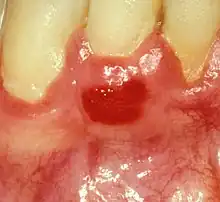

| Plasma cell gingivitis in an adult (histologically verified). |

Plasma cell gingivitis appears as mild gingival enlargement and may extend from the free marginal gingiva on to the attached gingiva.[6] Sometimes it is blended with a marginal, plaque induced gingivitis, or it does not involve the free marginal gingiva. It may also be found as a solitude red area within the attached gingiva (pictures). In some cases the healing of a plaque-induced gingivitis or a periodontitis resolves a plasma cell gingivitis situated a few mm from the earlier plaque-infected marginal gingiva. In case of one or few solitary areas of plasma cell gingivitis, no symptoms are reported from the patient. Most often solitary entities are therefore found by the dentist.[2]

The gums are red, friable, or sometimes granular, and sometimes bleed easily if traumatised.[6] The normal stippling is lost.[7] There is not usually any loss of periodontal attachment.[6] In a few cases a sore mouth can develop, and if so pain is sometimes made worse by toothpastes, or hot or spicy food.[7] The lesions can extend to involve the palate.[7]